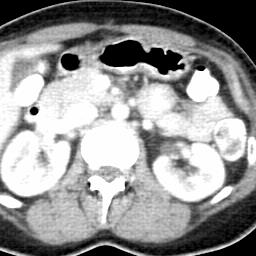

Due to the constraints of the imaging device and high cost in operation time, computer tomography (CT) scans are usually acquired with low intra-slice resolution. Improving the intra-slice resolution is beneficial to the disease diagnosis for both human experts and computer-aided systems. To this end, this paper builds a novel medical slice synthesis to increase the between-slice resolution. Considering that the ground-truth intermediate medical slices are always absent in clinical practice, we introduce the incremental cross-view mutual distillation strategy to accomplish this task in the self-supervised learning manner. Specifically, we model this problem from three different views: slice-wise interpolation from axial view and pixel-wise interpolation from coronal and sagittal views. Under this circumstance, the models learned from different views can distill valuable knowledge to guide the learning processes of each other. We can repeat this process to make the models synthesize intermediate slice data with increasing inter-slice resolution. To demonstrate the effectiveness of the proposed approach, we conduct comprehensive experiments on a large-scale CT dataset. Quantitative and qualitative comparison results show that our method outperforms state-of-the-art algorithms by clear margins.